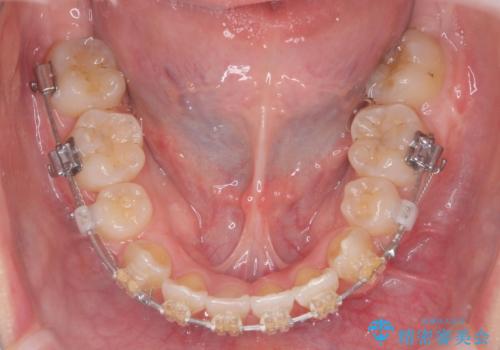

突き出た前歯を治したい 小臼歯抜歯+マルチブラケット矯正

- 矯正装置

- ワイヤー矯正

前歯の角度を改善するために小臼歯4本の抜歯を行いワイヤー マルチブラケットを用いて、しっかりと前歯の角度を改善する治療計画としました。

綺麗な歯並びを手に入れられたと同時に、口元もスッキリし、仕上がりに満足いただくことができました。